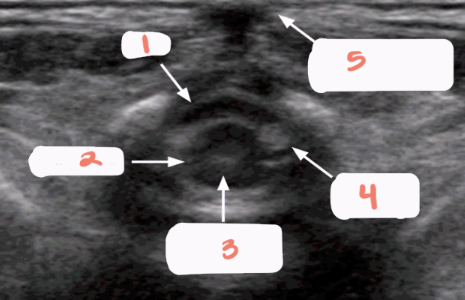

1

spinous processes

2

subarachnoid/dural layer

3

subarachnoid space filled with CSF

4

posterior margin of spinal cord

5

spinal cord with central echo complex

6

anterior margin of the spinal cord